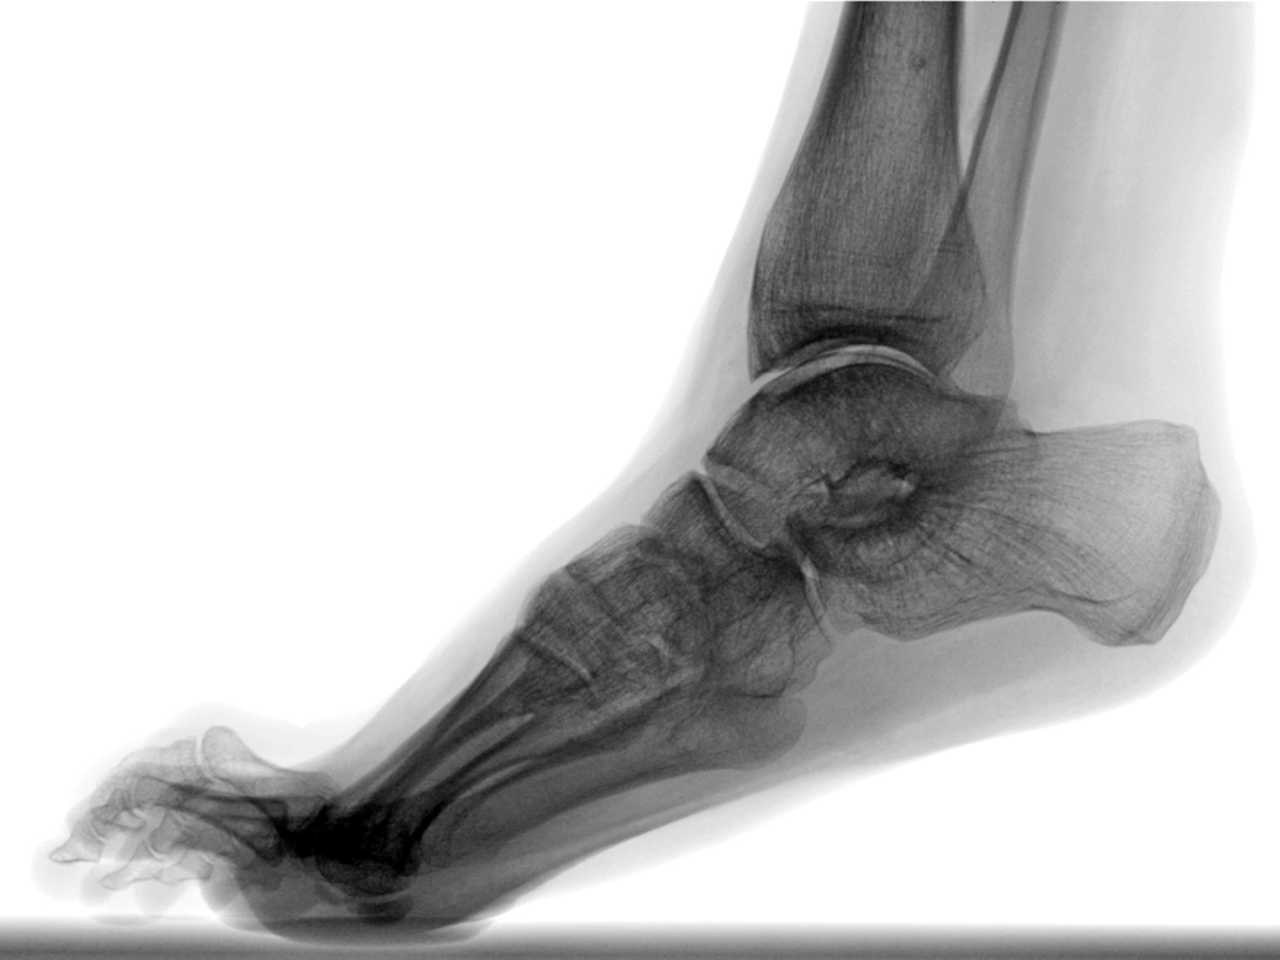

Крім того, припускають, що носіння підборів з часом призводить до еквінусу — дискомфорту при спробах потягнути пальці ноги на себе чи неможливості це зробити. У людей з цією патологією нога залишається у такому положенні, як в «ідеальної» Барбі, тобто постійно навшпиньки.

Хоча науковці сумніваються у деяких доказах шкідливості носіння підборів і закликають провести детальніші дослідження цього, з одним сперечатися важко: взуття з підборами впливає на темп ходьби. Мало того, що у такому взутті зменшується швидкість ходьби та ширина кроку, так ще й підвищується нестабільність гомілкового суглоба, а з нею й імовірність падіння. Усе це разом робить взуття на підборах незручним для роботи у реальному житті, але чи працює ця логіка у Барбіленді, тобто світі Барбі?